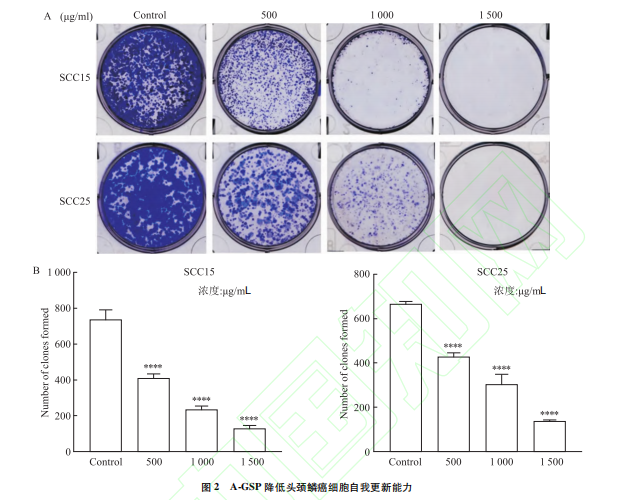

科研新知|去壁灵芝孢子粉水溶成分抑制头颈鳞癌细胞增殖转移

2024-03-15 14:33 发表